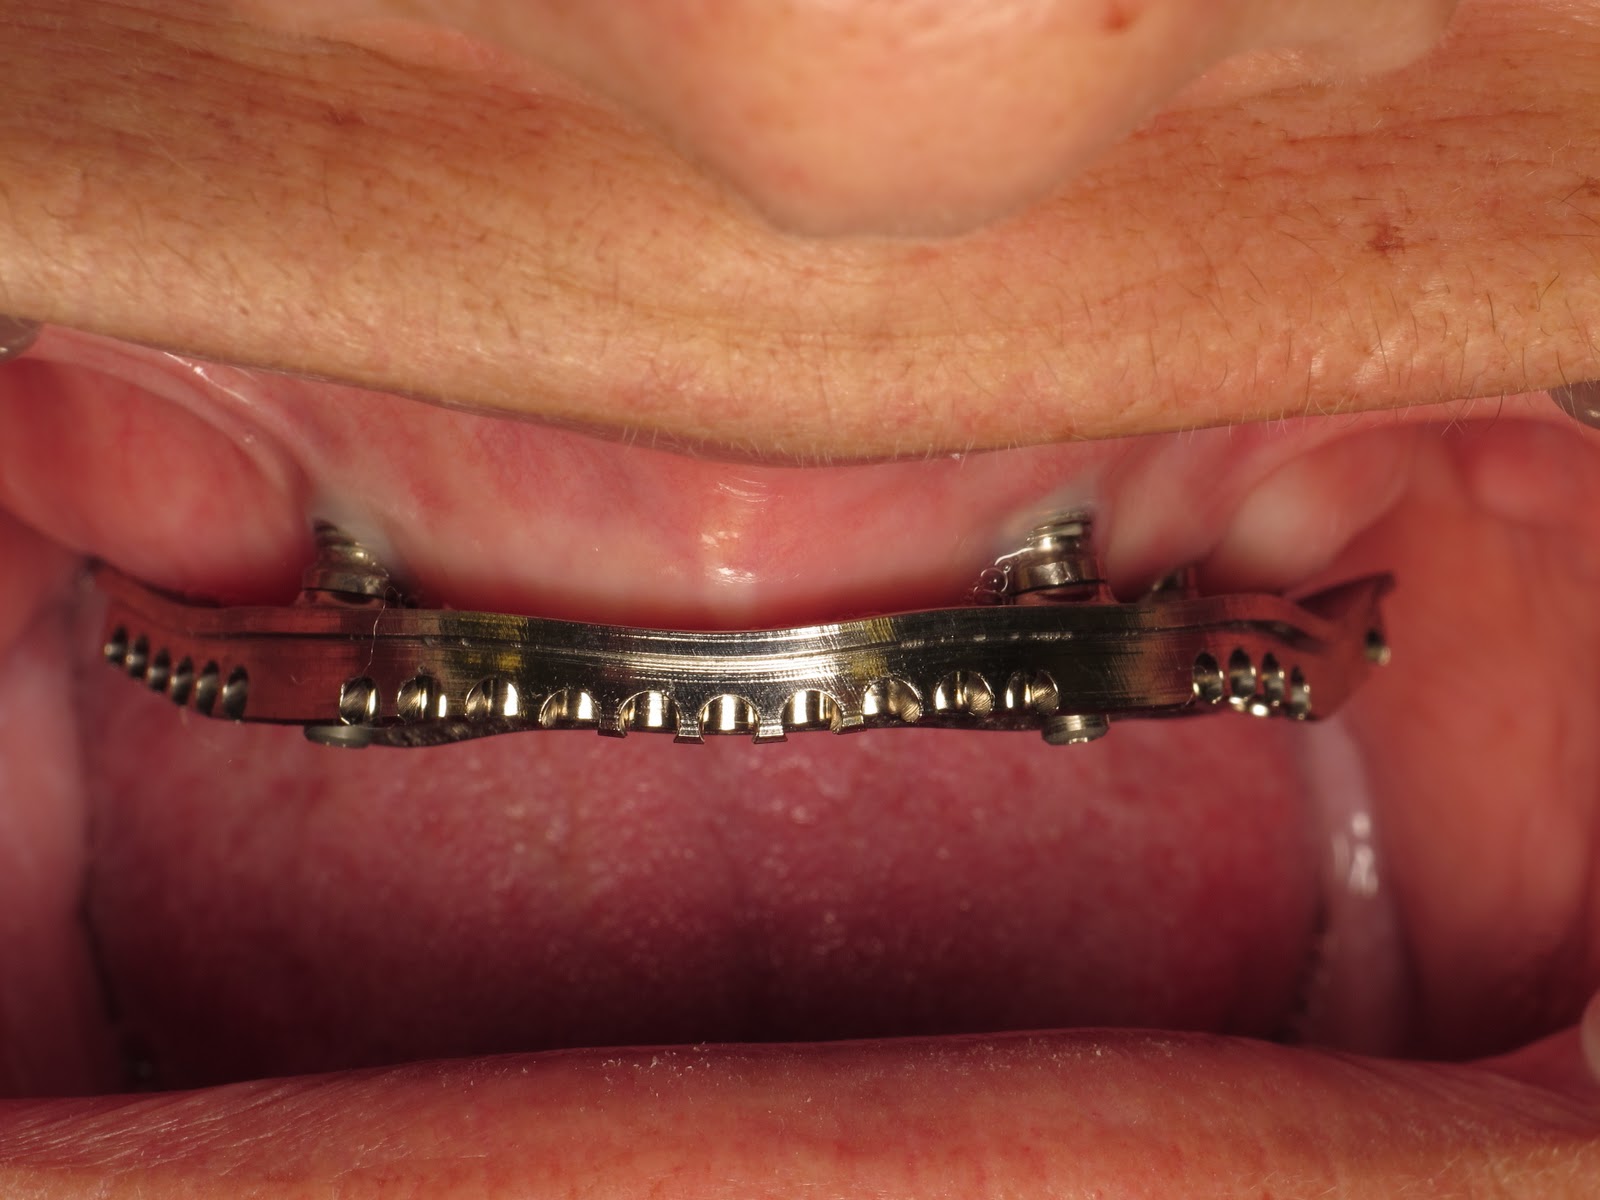

From www.vdsclinic.com

Implant Supported Overdenture Permanent Dentures Vancouver BC Titanium Bar For Dental Implants    titanium bars are renowned for their exceptional strength and durability, which are crucial attributes for dental. The prosthetic arch, however, may need replacing at some stage.  thanks to its exceptional strength and corrosion resistance, the alien implant titanium bar is capable of supporting multiple dental prosthetics, including.   cad/cam technology allows us to use a titanium bar that. Titanium Bar For Dental Implants.